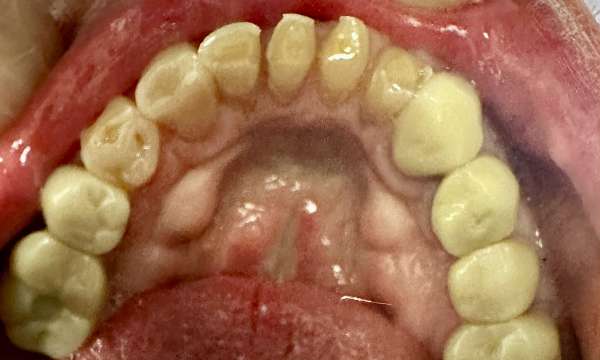

Fixing Broken Teeth

This patient came to us with broken teeth. Dental crowns gave them a more aesthetic appearance and improved their oral health.